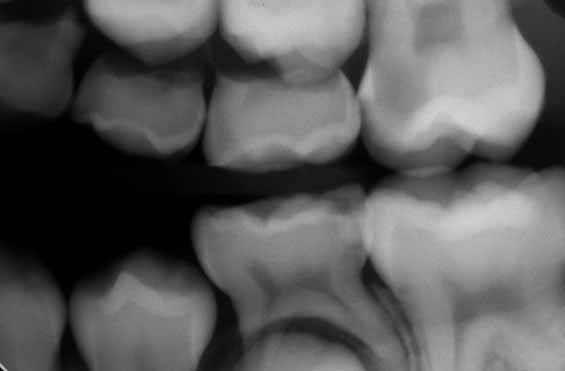

画像診断

個々の適応に応じてX線検査を実施する必要があります。隣接面接触点や虫歯の疑い、異所萌出の疑いなど、他の方法では得られない重要な診断にX線検査が役立つと判断される場合です。